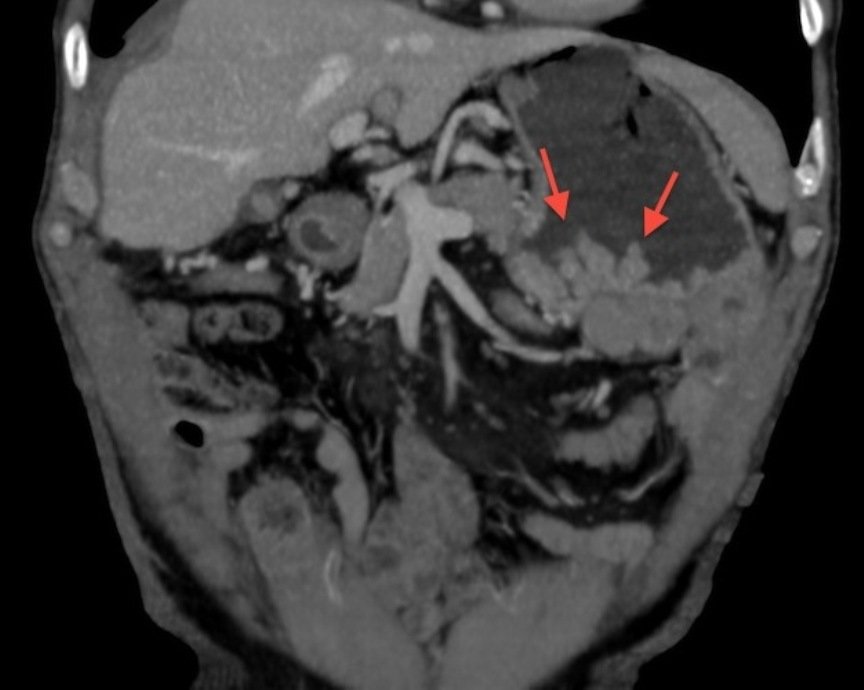

- эндоскопическое исследование – фиброгастроскопия, которая выполняется при помощи эзофагогастроскопа, при осмотре хорошо видны образовавшиеся утолщением складки, которые напоминают мозговые извилины — так называемый симптом «булыжной мостовой»;

Для эндоскопической картины болезни Менетрие характерны наличие резко утолщенных складок слизистой в теле желудка по большой кривизне, принимающих вид мозговых извилин или «булыжной мостовой», легкая ранимость их, эрозии, геморрагии, большое количество слизи.